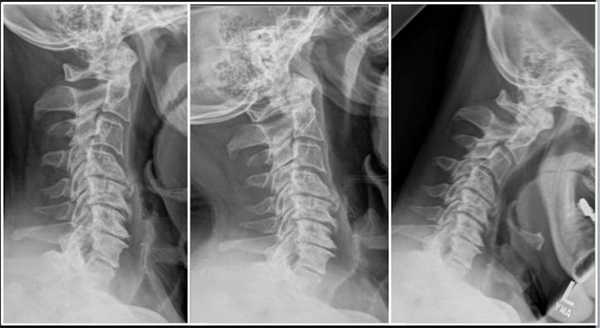

- Рентгенография позвоночника. Высота межпозвоночных дисков снижена. На снимках просматриваются распространенные дегенеративные изменения, определяются остеофиты, выступающие в сторону спинномозгового канала.

- Рентгенография позвоночника. Исследование информативно спустя 3-6 недель от начала заболевания. На рентгенологических снимках обнаруживают деструкцию тел позвонков, эрозию замыкательных пластин, уменьшение расстояния между соседними позвонками. Для более четкой визуализации назначается КТ позвоночника.